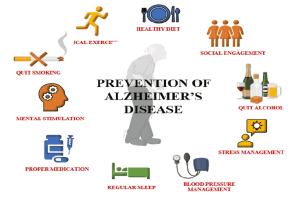

بررسی کامل عوامل خطر آلزایمر: آیا جنسیت و دیگر عوامل نقش دارند؟

مراحل پیشرفت بیماری آلزایمر

بهترین رژیم غذایی پیشگیری از آلزایمر

عوامل موثر در بروز آلزایمر: چه چیزهایی خطر ابتلا را افزایش میدهد؟

نشانه های اولیه آلزایمر: 10 علامتی که نباید نادیده بگیرید

شش راهکار موثر برای پیشگیری از ابتلا به بیماری آلزایمر